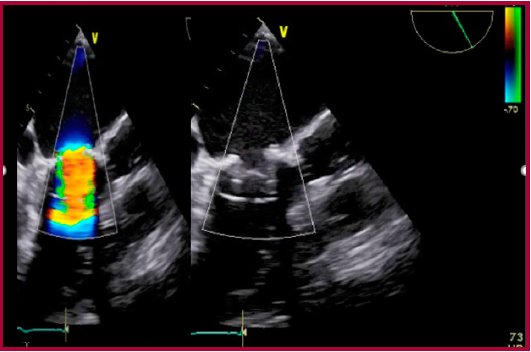

Se encontraba con disnea en clase funcional II, la cual progresa en los últimos meses a clase funcional III. En el ETT (ecocardiograma transtorácico), se observa insuficiencia mitral grave con jet excéntrico con efecto Coanda hasta el techo auricular, marcado colapso de ambas valvas. Insuficiencia tricúspidea grave con PSAP (presión sistólica de arteria pulmonar) de 75 mmHg. FSVI (Función sistólica ventricular izquierda) leve a moderada con FEY (Fracción de eyección) del 50%. Aquinesia inferior, inferolateral y septal posterior. Se realizó cinecoronariografía, en la que presentó una lesión moderada del tronco coronario izquierdo, lesión grave en la arteria descendente anterior, lesión grave en la arteria circunfleja, oclusión total de la arteria coronaria derecha; ambos bypass venosos se encontraban ocluidos. Se presentó el caso en el ateneo clínico-quirúrgico del servicio de cardiología, en el que se decidió realizar un implante valvular percutáneo en posición mitral (valve-in-valve) y el ingreso de la paciente al programa de cardiopatía estructural de la institución.

Se realizó bajo anestesia general y con apoyo de ecocardiografía transesofágica (ETE) con la cual se descartó la presencia de trombos. Con una minitoracotomía al nivel del quinto/sexto espacio intercostal anterior izquierdo y posterior apertura del pericardio, se aseguró con dos puntos de sutura concéntricas triangulares con prolene 3-0. Se realizó una punción directa del ápex y se avanzó una guía blanda que se intercambió por una guía ExtraStiff de 0,035” en la aurícula izquierda. Se corroboró bajo visión por ETE principalmente, ya que la válvula biológica implantada no nos proporcionaba bordes radiolúcidos como guía, de gran importancia para el posicionamiento; 6 esto se realizó en forma indirecta a través de un catéter cola de cerdo (pig tail) en el ventrículo izquierdo, la posición adecuada de la válvula Edwards balón-expandible SAPIENT XT número 26 (Figura 1), y, a través de marcapaseo rápido a 180 latidos por minuto, se expandió el balón y se desplegó la válvula, se controló por radioscopia, ventriculografía y ETE, su correcto funcionamiento, sin fugas paravalvulares, por lo que se dio por terminado el procedimiento en forma exitosa (Figura 2). La paciente pasó a unidad coronaria y a los 4 días fue dada de alta sin complicaciones.

En el ETT control, anterior al egreso y al mes posintervención, se observó la prótesis normofuncionante con gradientes adecuados.